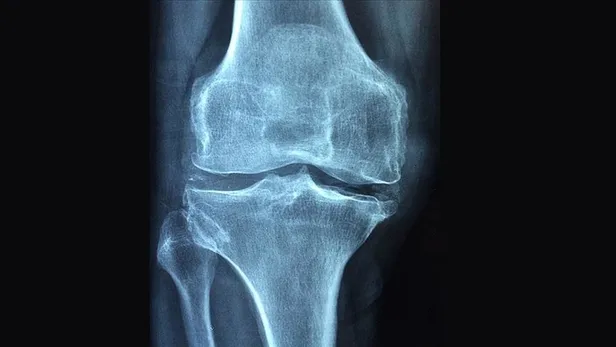

Romatizma ağrım arttı. İlaçlar mide kanaması yapmıştı. Doz arttıramıyorum. Siz daha önce ozon tedavisini önermiştiniz. Bana faydalı olur mu?

Ozon tedavisi özellikle ağrıların tedavisinde kullanılan bir tedavi yöntemi. Doğru ve hastaya uygun uygulamalarda beklenen bir yan etki yok. Ağrı kontrolünde oldukça önemli faydaları var. Kişiye göre planlanan tekrarlayıcı uygulamalarla ağrıların azaldığı biliniyor. Size de bu yöntem uygulanabilir.